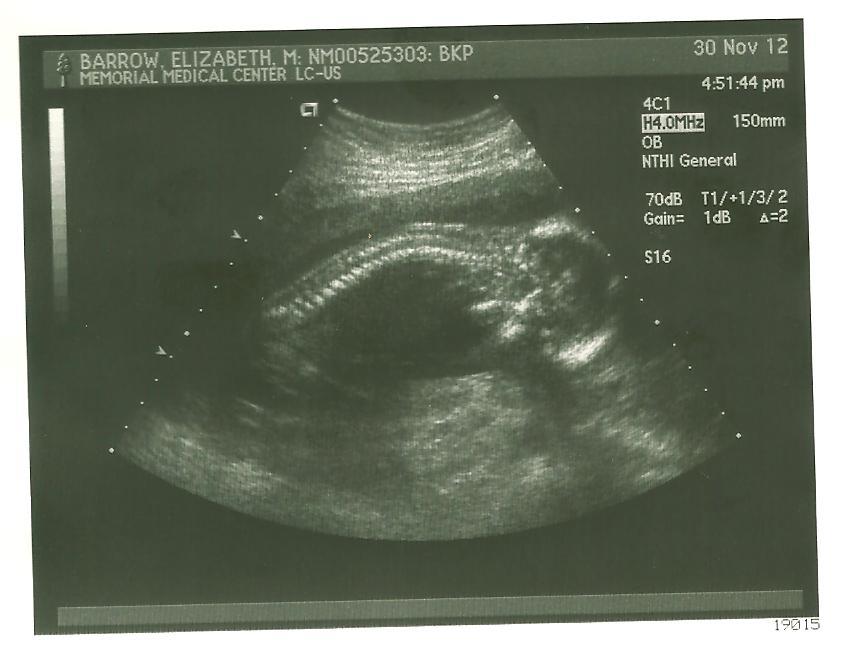

ultrasound3

Ultrasound Time!